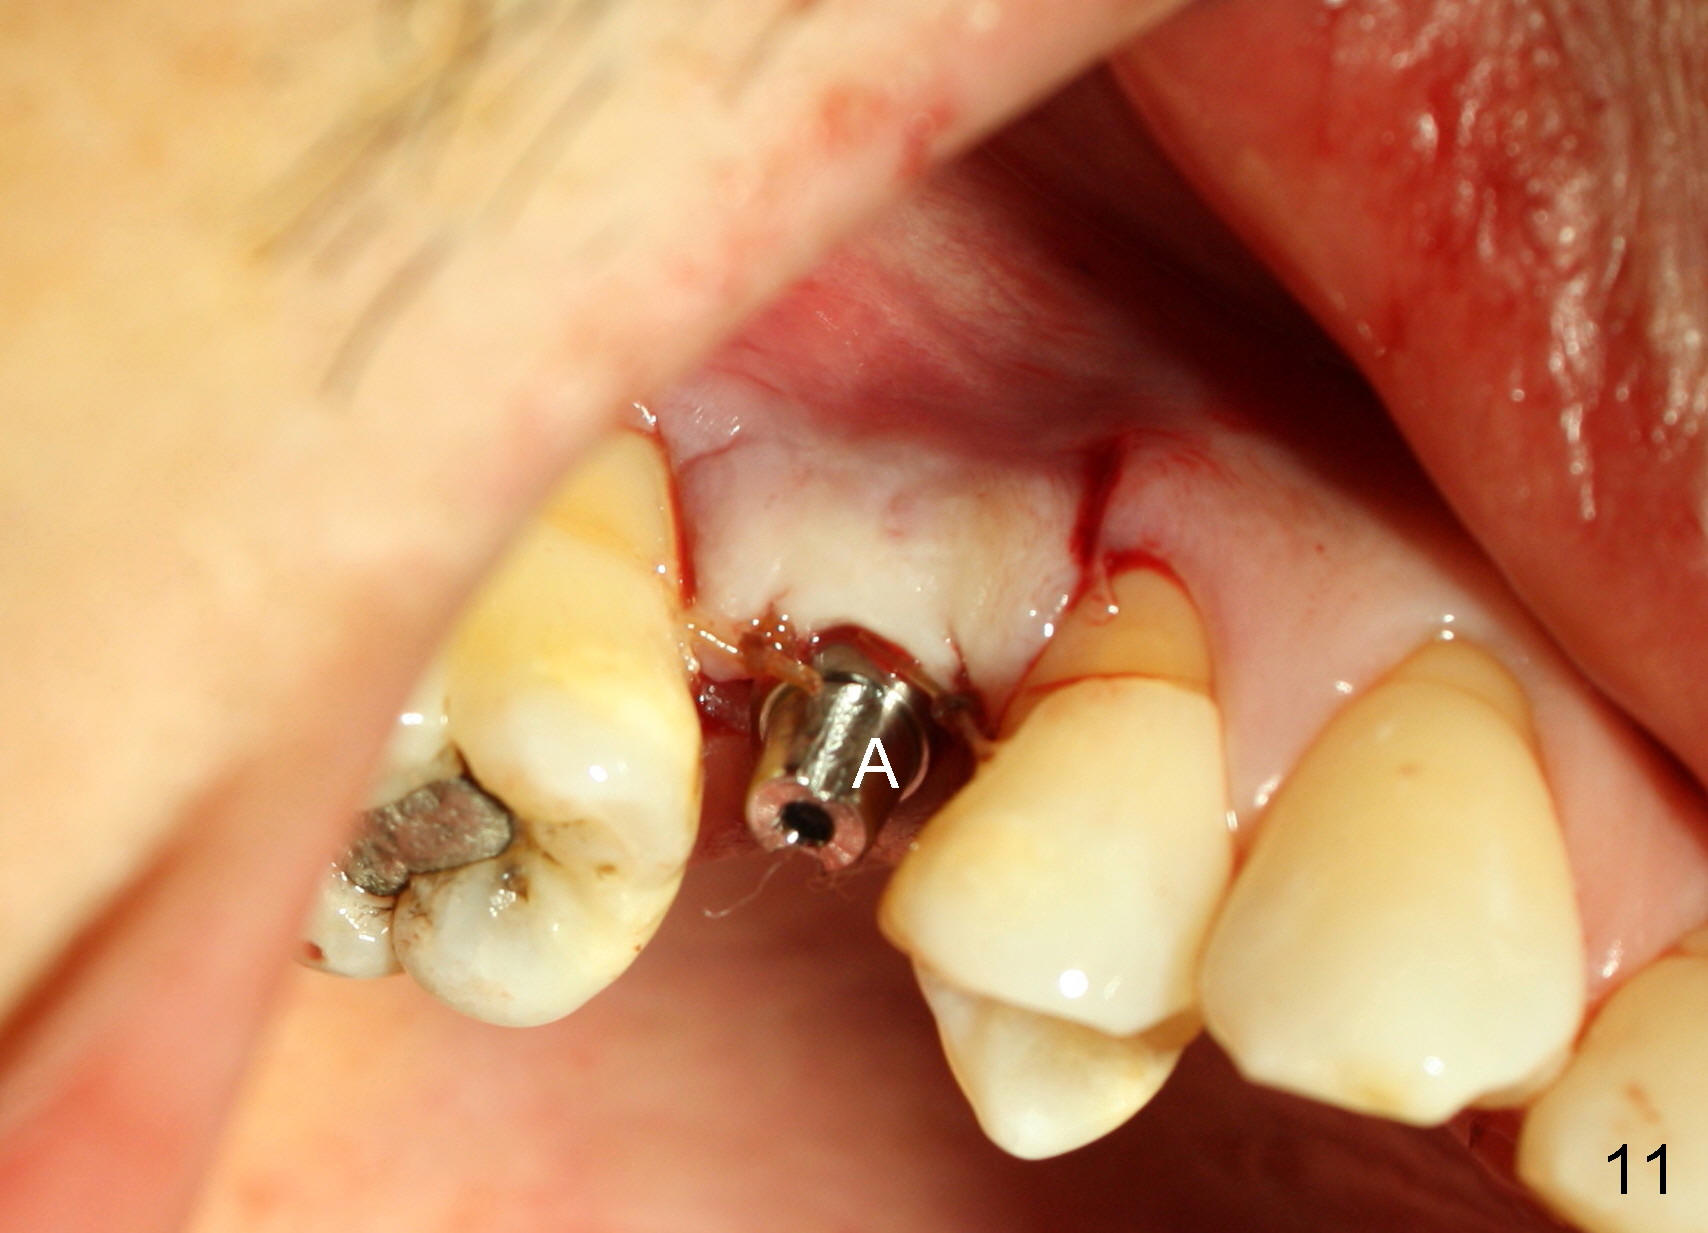

The tooth #4 was removed from a 41-year-old man (Fig.1). Fig.2 was taken 1 year and 7 months post extraction. Osteotomes (Fig.3,4) were used to create osteotomy (7 yr 9 m post ext). A 4x14 mm implant was placed below the sinus floor with insertion torque > 60 Ncm (Fig.5). The surgery was flapless (Fig.6). No antibiotic was taken pre- and post-op. The implant was found to be tender and loose. It was removed without bone graft.

Nine months later, the patient returned for re-implantation (Fig.7). Amoxicillin and Chlorhexidine were used preop and postop. Flaps were raised for better vision of reimplantation site (Fig.8). Bone density was high (type II). Drills were used to form osteotomy (Fig.9). A 4x17 mm implant was placed with internal sinus lift (Fig.10*). The insertion torque was also >60 Ncm. The flaps were approximated and a short abutment (Fig.11 A) was placed to hold perio dressing in place.